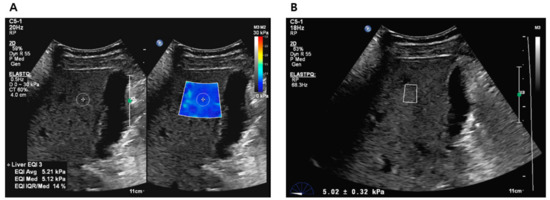

2.2. Liver Stiffness Values Measurement Using 2D-SWE and p-SWE